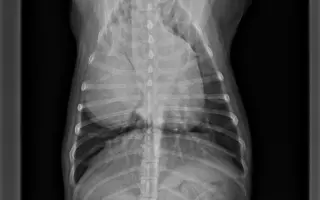

Bessie v piatok absolvovala prvú pooperačnú kontrolu, ktorá dopadla super. Všetko ide tak ako má, rana sa hojí pekne. Kontrolné rentgeny dopadli dobre, všetko je v poriadku.

Tak a máme výsledky z CT a biopsie. CTčko nám ukázalo, že Bessie má nádor na pravom pľúcnom laloku o veľkosti 9,9 × 9 × 4,3 cm. Aktuálne jej tlači na zadnú dutú žilu, v dôsledku čoho jej už opúcha pečeň. Nádor je však jeden, solídny a žiadne ďalšie metastázy sa nepotvrdili. Čo však ukázala biopsia, je že nádor je zhubný a ide o primárny karcinóm pľúc.

Termín operácie mala 17. 11., kde jej operáciu mali na starosti MVDr. Valášek a MVDr. Valašek Nusová. Nás čakali najťažsie hodiny, kedy sme len čakali na telefónat z VetPointu. Nakoniec operácia trvala až 2,5 hodiny, nádor odo dňa kedy sa robilo CT, narástol na 10×9,5×5 cm, čo nám len potvrdilo, že rástol extrémne rýchlo. Môžme povedať, že jej operácia zachránila život. Bessie bola na klinike hospitalizovaná do 19. 11. od kedy je v domácej liečbe. Pomaly sa zotavuje a zvláda to veľmi statočne. Prvá noc doma bola náročná, ale už sa z nej stáva opäť veselá Bessie, ktorá vôbec nekašle.